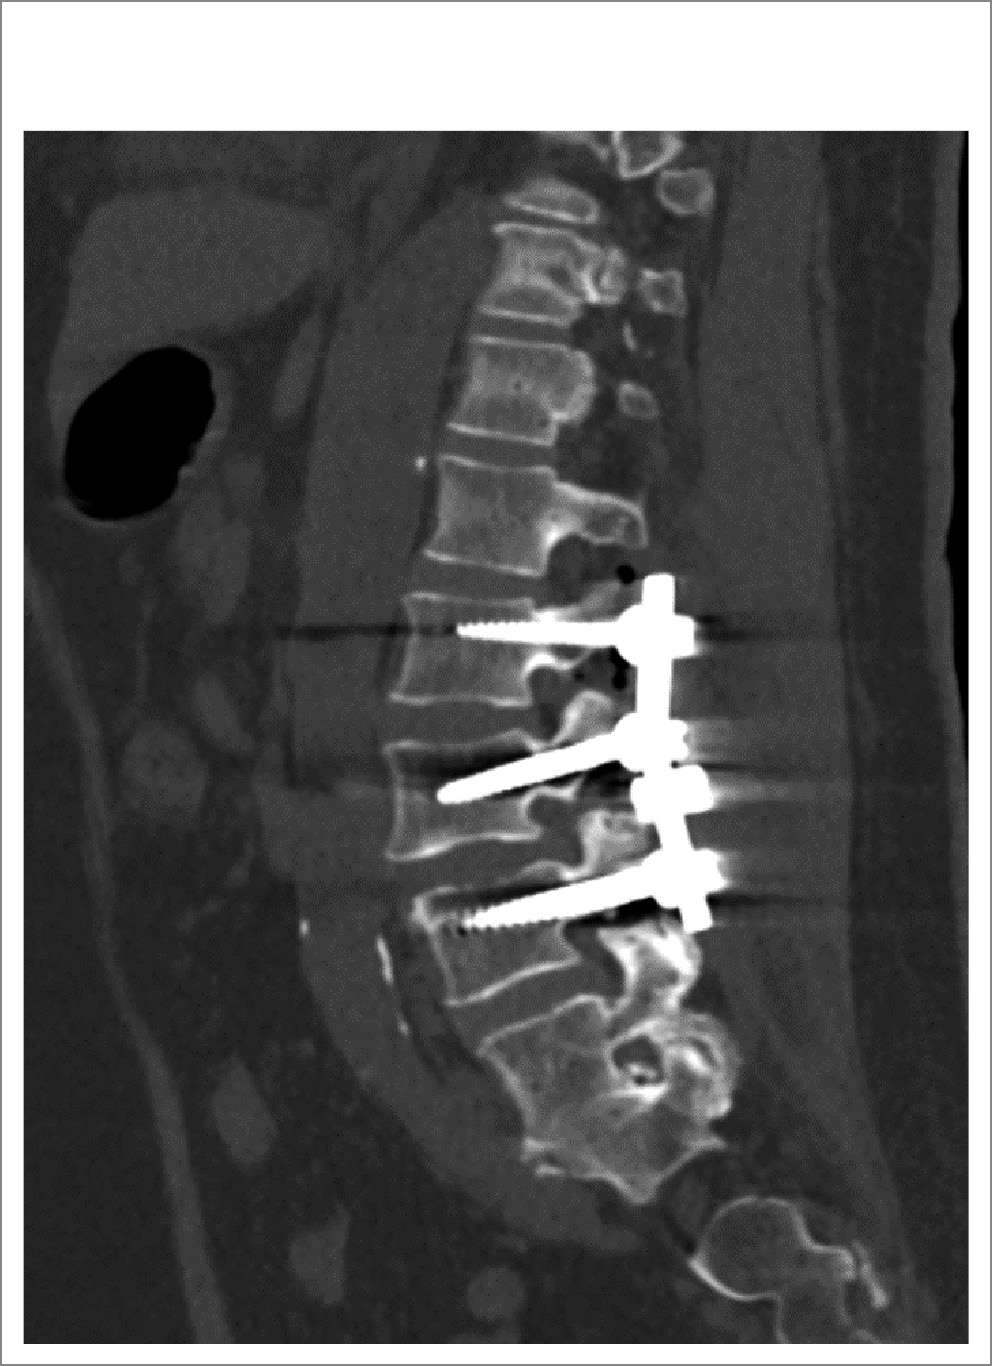

При магнитно-резонансной томографии пояснично-крестцового отдела позвоночника (20.03.2023) обнаружены дегенеративно-дистрофические изменения пояснично-крестцового отдела позвоночника в форме билатеральной сублигаментарной экструзии LIII–LIV до 0,5 см, гипертрофии желтых связок до 0,5 см, спондилоартроза, лестничного антелистеза тел LIII–LIV. Сагиттальный размер дурального мешка (ДМ) на уровне LIII–LIV составлял 0,6 см, что указывает на стеноз ПК на уровне LIII–LIV (рис. 1).

Рис. 1. Аксиальная проекция на уровне межпозвоночного диска LIII–LIV, сужение центрального спиномозгового канала; сужение латеральных карманов, больше слева.

Таким образом, в приведенном клиническом случае у пациентки отмечали смешанный ПС по данным нейровизуализации (сагиттальный размер ДМ на уровне LIII–LIV – 0,6 см, сужение латеральных карманов, больше слева). Учитывая полифакторность дегенеративного стеноза (билатеральную сублигаментарную экструзию, гипертрофию желтых связок, гипертрофию фасеточных суставов, лестничный антелистез тел LIII, LIV), боль в ПО позвоночника и НПХ, а также отсутствие эффекта от КЛ, принято решение о проведении декомпрессии на уровне стеноза с установкой транспедикулярных металлофиксаторов LII–LIII–LIV.